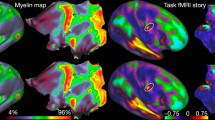

There are several approaches to brain parcellation that all carry utility for different applications. Boundary mapping based on local features may segregate the brain according to gross anatomy, cytoarchitecture and myelin density, while connectivity-based approaches use global brain features such as functional connectivity and white matter connectivity26,27. One benefit of local boundary mapping is that it may offer a more intuitive regional segregation. Many prior studies have utilized data-driven, local boundary mapping approaches to parcellation, for instance using resting-state fMRI to identify cortical parcels based on changes in functional connectivity patterns28,29. These methods produced parcellations that showed homogeneity with known brain network maps, as well as with architectonically derived maps, suggesting that a true biological feature was identified. Boundary mapping based on cytoarchitecture is another local feature mapping method that began with Korbinian Brodmann’s seminal work, and has continued to develop with the advent of the Julich Brain recently30,31. The Destrieux atlas is a local, boundary-based atlas created using gross neuroanatomical boundaries including sulci and fissures14. While the approach lends itself to usability, since gross neuroanatomy is a widely recognized language for brain localization, it could be enhanced with precise sub-gyral localization, which may be required in many studies.

The workflow used to create the atlas and the methods used to assess the accuracy and usefulness of the YBA for clinical application. The workflow is demonstrated in (A–F) using the temporal lobe for illustration. (A) The ICBM (MNI) 152 template was labelled anatomically using designations in Duvernoy’s Atlas of the Human Brain. (B) Boundaries were created for the Yale Brain Atlas (YBA) between major anatomical landmarks to distinguish the lobar and sub-lobar regions. (C) The YBA anatomical boundaries were checked against 25 individual MRI scans to assess validity. (D) Cortical surface measures were used between major atlas boundaries to identify the number of parcels in each region. The middle temporal gyrus was approximately two-centimeters in width, so it was split in two to maintain the one-square centimeter parcellation. (E) The temporal body was parcellated into superior temporal, middle temporal, and inferior temporal regions. (F) The parcellation was continued across the entire MNI152 template to create the YBA. (G) The first step in evaluation anatomical accuracy was to use intraoperative images as a ‘ground truth’ for electrode contact localization and relate the contacts to topographical neuroanatomy. (H) MR imaging for each patient was compared with that patient’s ground truth, intraoperative image for accuracy. Once the electrode localizations were verified as accurate, the electrodes were transformed to the MNI152 brain. (I) The YBA parcellation was labelled according to the electrode locations to facilitate precise, cohort-wide localization.